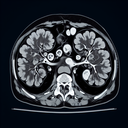

МРТ нирок

МРТ нирок — це неінвазивне дослідження, яке дозволяє отримати детальні зображення нирок та прилеглих структур. Метод використовує магнітне поле та радіохвилі для створення якісних зображень. ### Основні показання до МРТ нирок: - Підозра на пухлини або кісти...